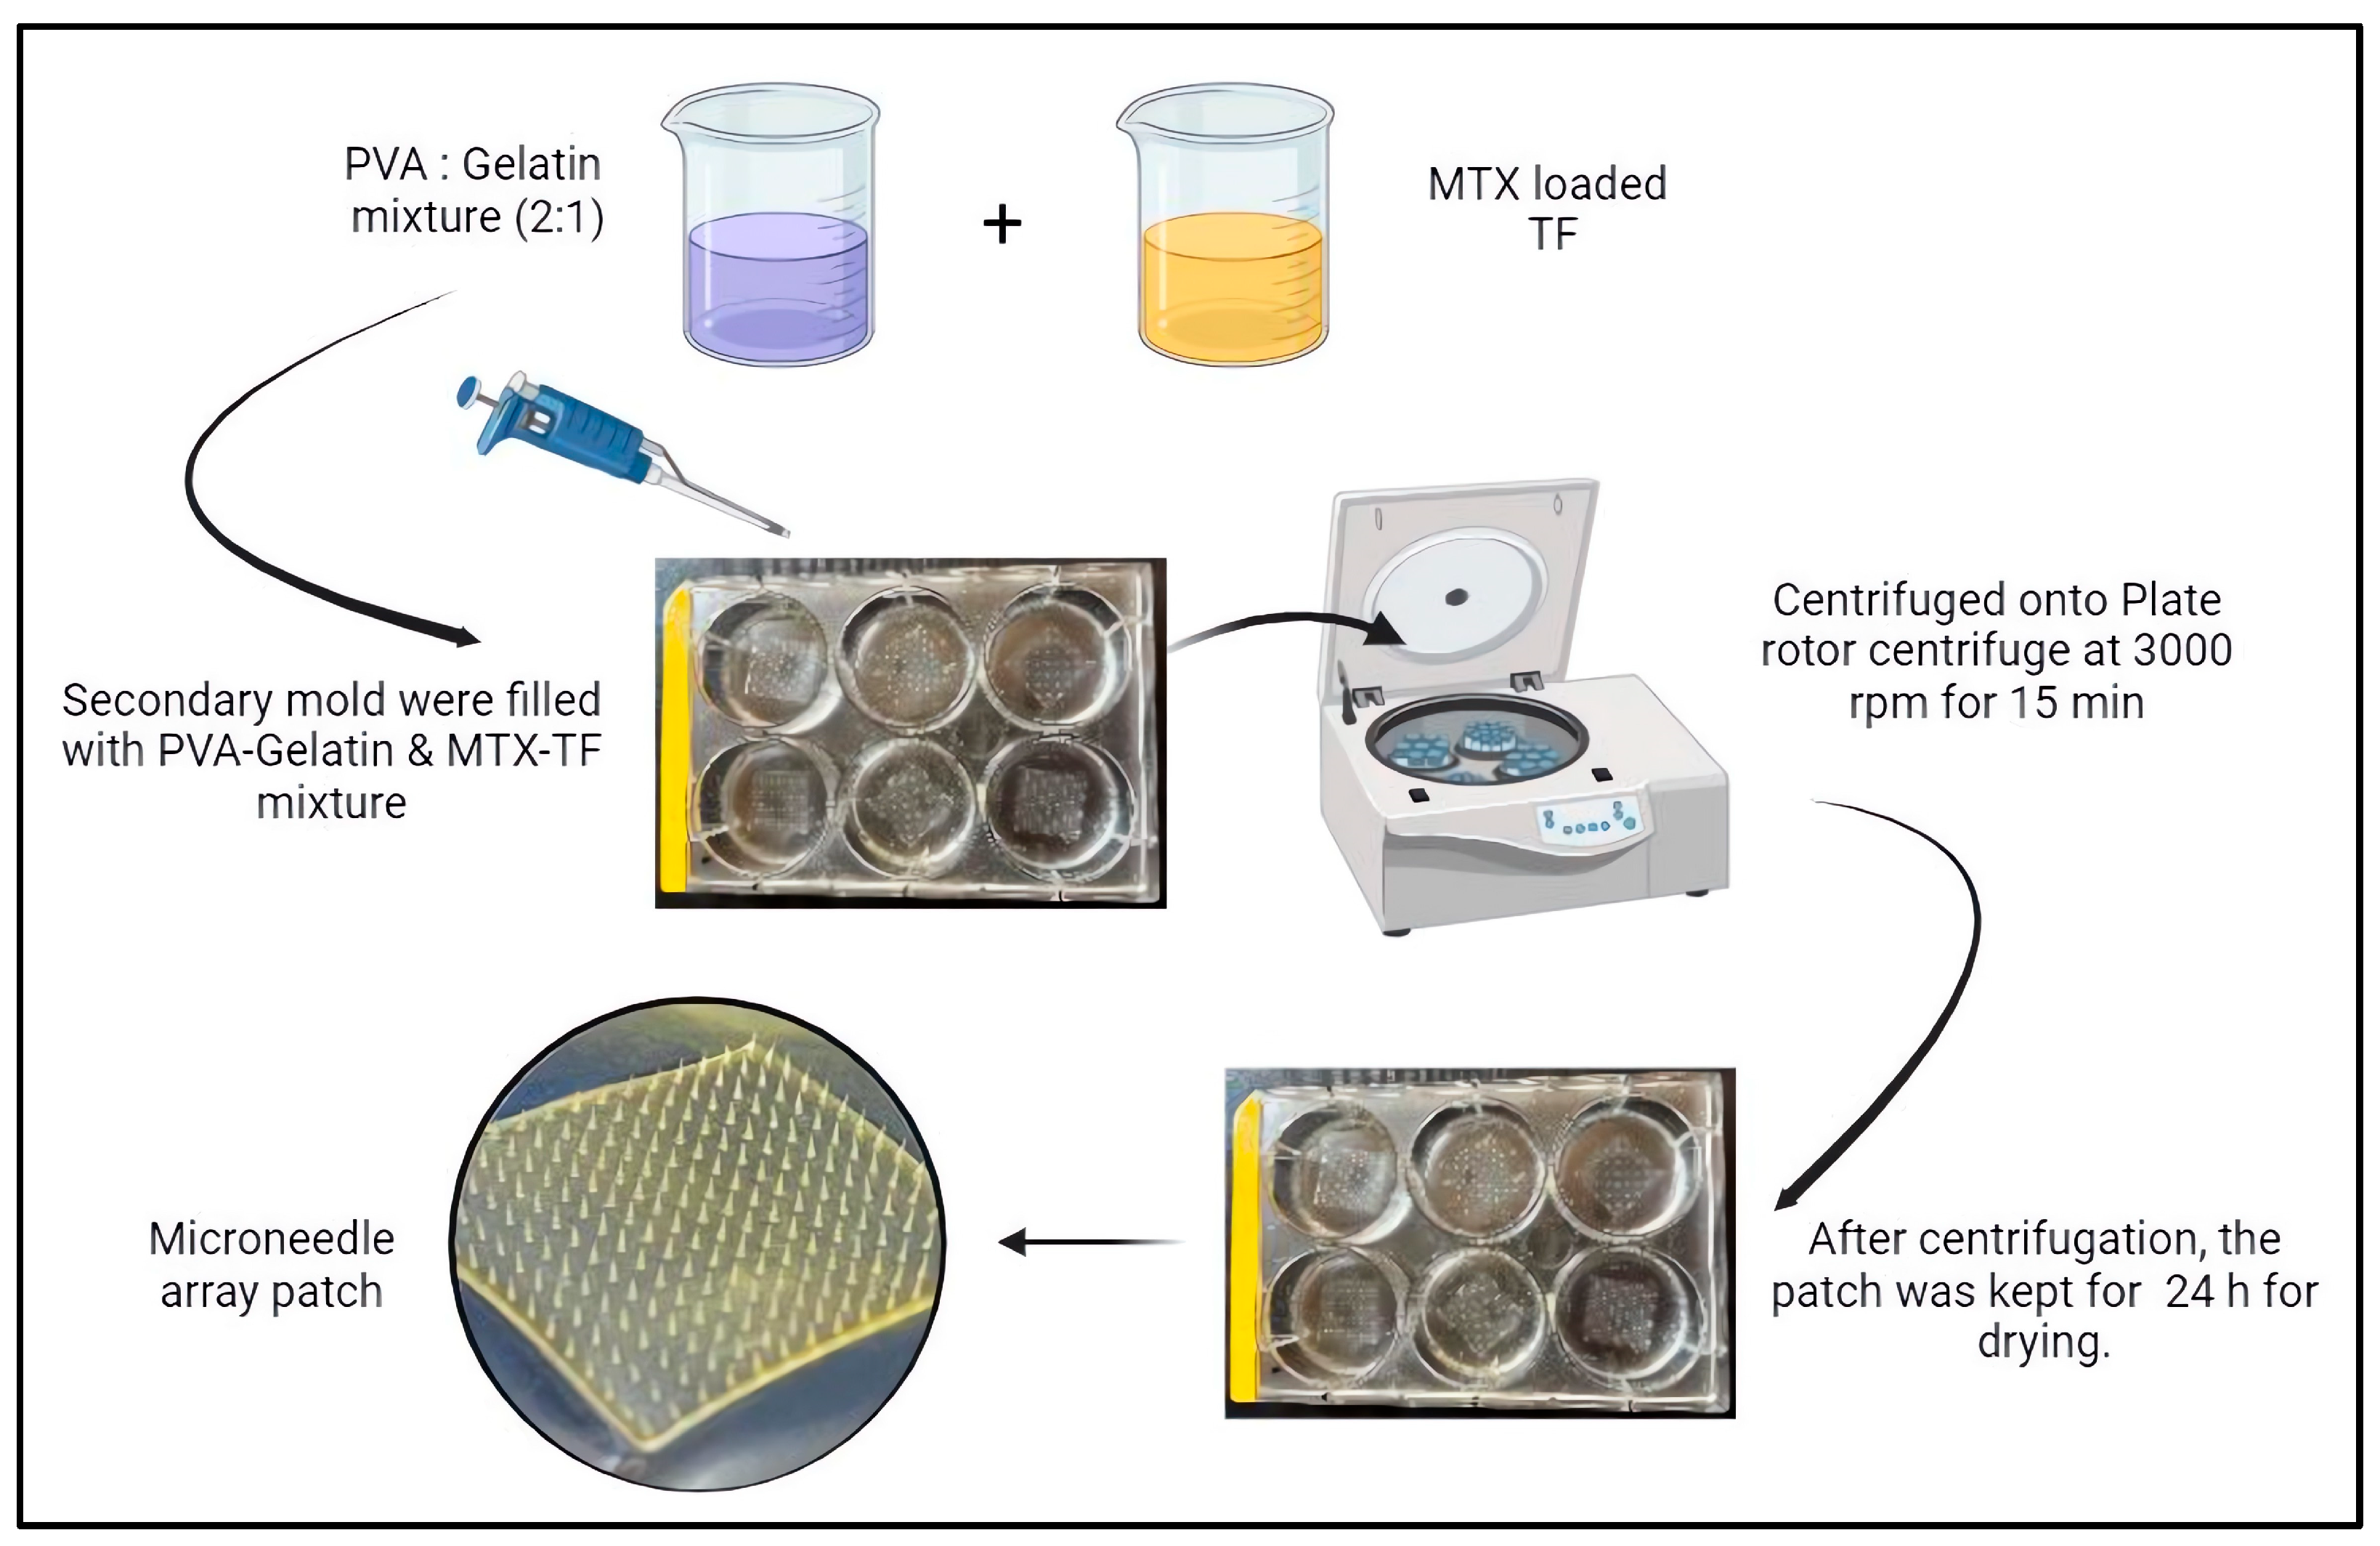

3.3. Fabrication of Microneedle Array Patch

3.4. Morphological Characterization of MTX-TF-Loaded MNs

3.4.1. Optical Microscopy and Field Emission Scanning Electron Microscopy